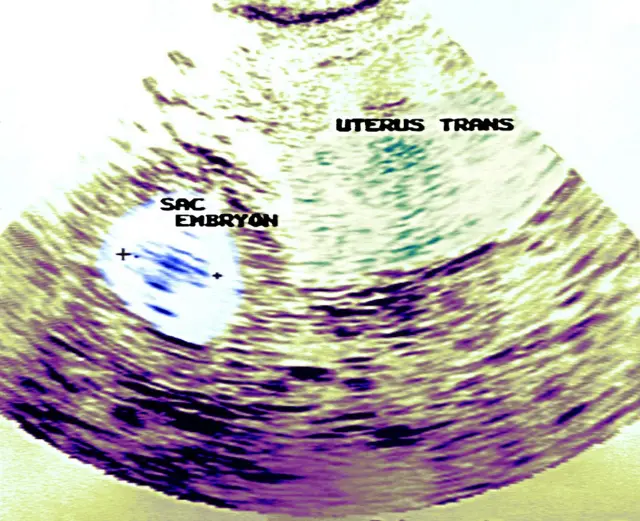

ایکٹوپک پریگننسی سے مراد ہے غیر معمولی حمل، جس میں بیضہ بچہ دانی کے اندر نہیں بلکہ اس کے باہر بننا شروع ہو جاتا ہے۔ ایسا حمل بیضہ دانی کے ساتھ فيلوپی نالیوں میں ٹھہرتا ہے تاہم یہ ایبڈومی میں یا سروِکس میں بھی ہو سکتا ہے۔

ماہر امراض نسواں ڈاکٹر مہناز عاصم نے بتایا کہ ایکٹوپک کے مطلب ہیں ایب نارمل یا غیر معمولی حمل۔ ایسا حمل بچہ دانی کے اندر نہیں بلکہ بچے دانی کے علاوہ کسی اور جگہ پر ٹھہر جاتا ہے۔ زیادہ تر یہ یوٹرس کے ساتھ فلوپین ٹیوبس میں ٹھہرتا ہے لیکن یہ ایبڈومنل بھی ہو سکتا ہے یا سرویکس، جو یوٹرس کا نچلا حصہ، میں بھی۔